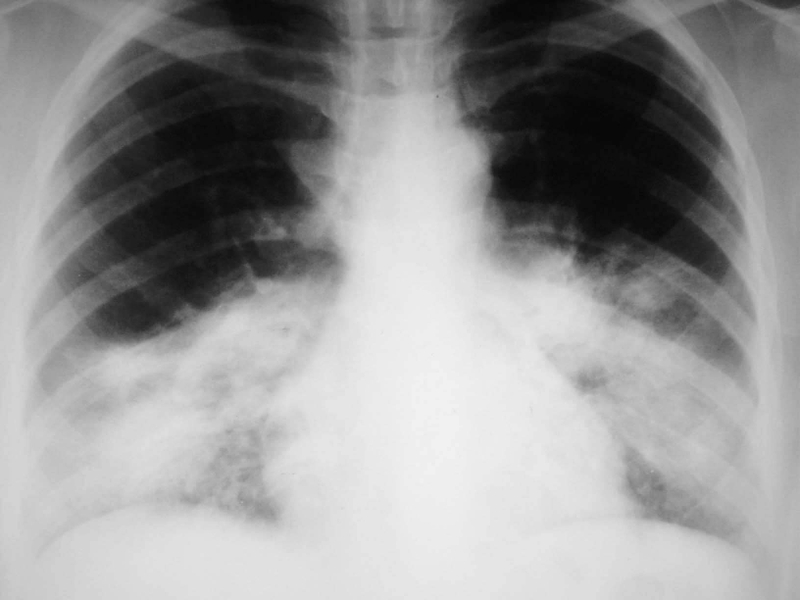

Dẫn lưu dịch màng phổi: Thực hiện khi lượng dịch chảy ra còn dưới 200ml/24 giờ, tình trạng bệnh nhân có dấu hiệu cải thiện và X-quang phổi cho thấy phổi đã nở hoàn toàn.